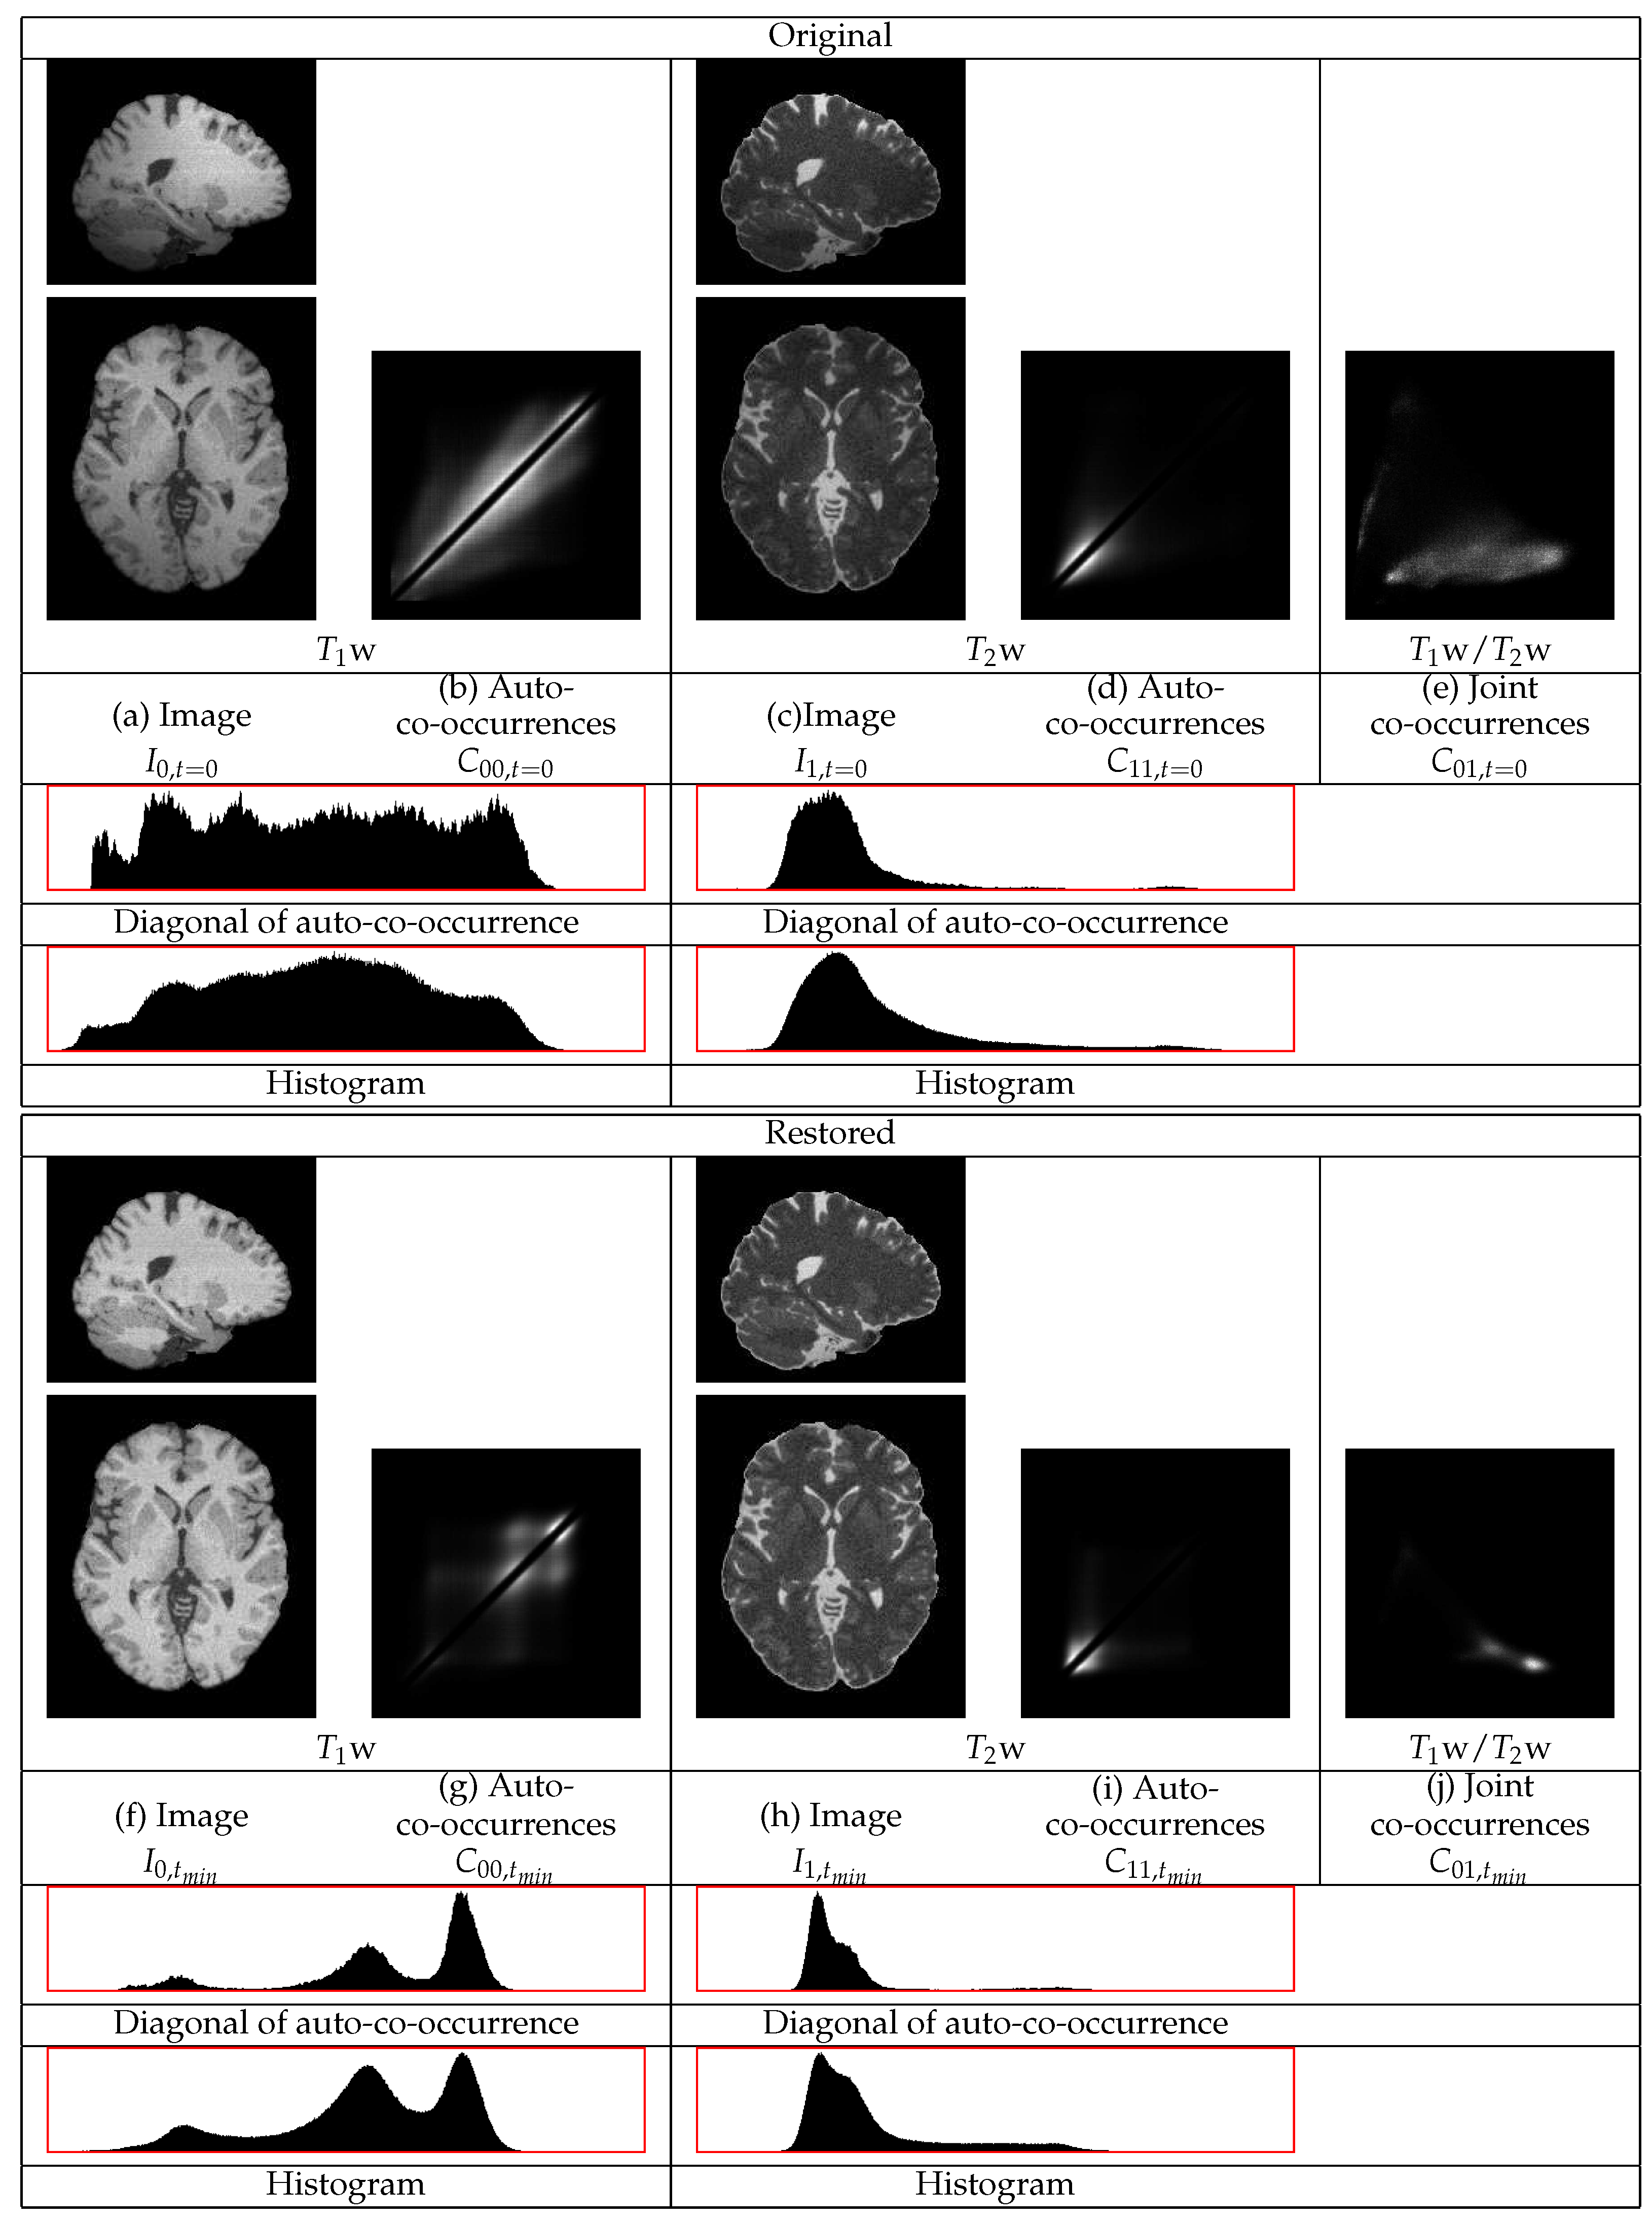

The restorations of the Brainweb phantom images with noise and with the highest level of non-uniformity, , are shown in Figure 5. This figure contains sections from the original and from the restored images as well as the co-occurrence statistics. In this example, the cerebellum in both the w and the w images becomes brighter and thus its statistics become closer to those of the corresponding mean tissue statistics over the remaining image regions.

Figure 5.

The restoration of a w and a w BrainWeb image pair with non-uniformity of and noise of . The restoration makes the cerebellum brighter and the statistics sharper.